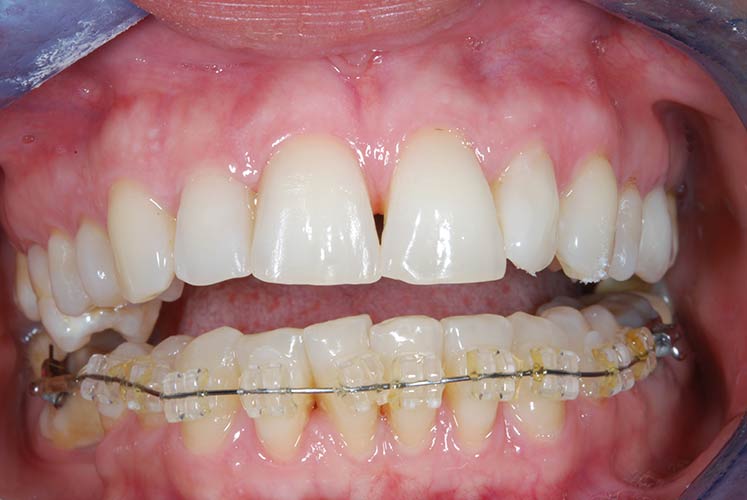

Con protesi fissa superiore e protesi fissa inferiore

I denti irrecuperabili dell'arcata superiore ed inferiore del paziente di anni 65

sono stati sostituiti da 10 impianti, cioè protesi radicolari endo-ossee che sostengono le protesi fisse superiore ed inferiore.